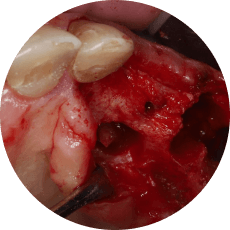

Атравматичное удаление ретенированных третьих моляров

Разрезы и типы лоскутов

Техника остеоэктомии

Навыки на уровне челюстно-лицевой хирургии: от удаления зачатка ретенированного нижнего третьего моляра до удаления горизонтально расположенных зубов.